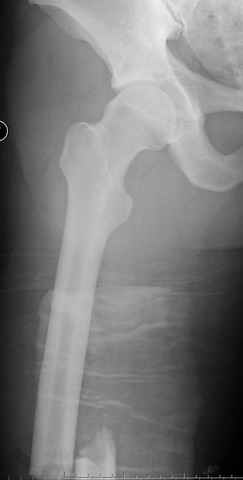

03.14.2005

больному 42, автоавария, политравма, открытая черепномозговая травма, безсознании, открытый перелом бедра, размозжение мягких тканей, дефект кожи на передней поверхности бедра около 13 см2 от ожога, компартмент синдром.

По поводу открытого перелома больной ургентно взят на ретроградное интрамедулярное штифтование, после рутинного дебрайдмента и фасциотомии на бедре и на голени.

перелом бедра

постоперационные